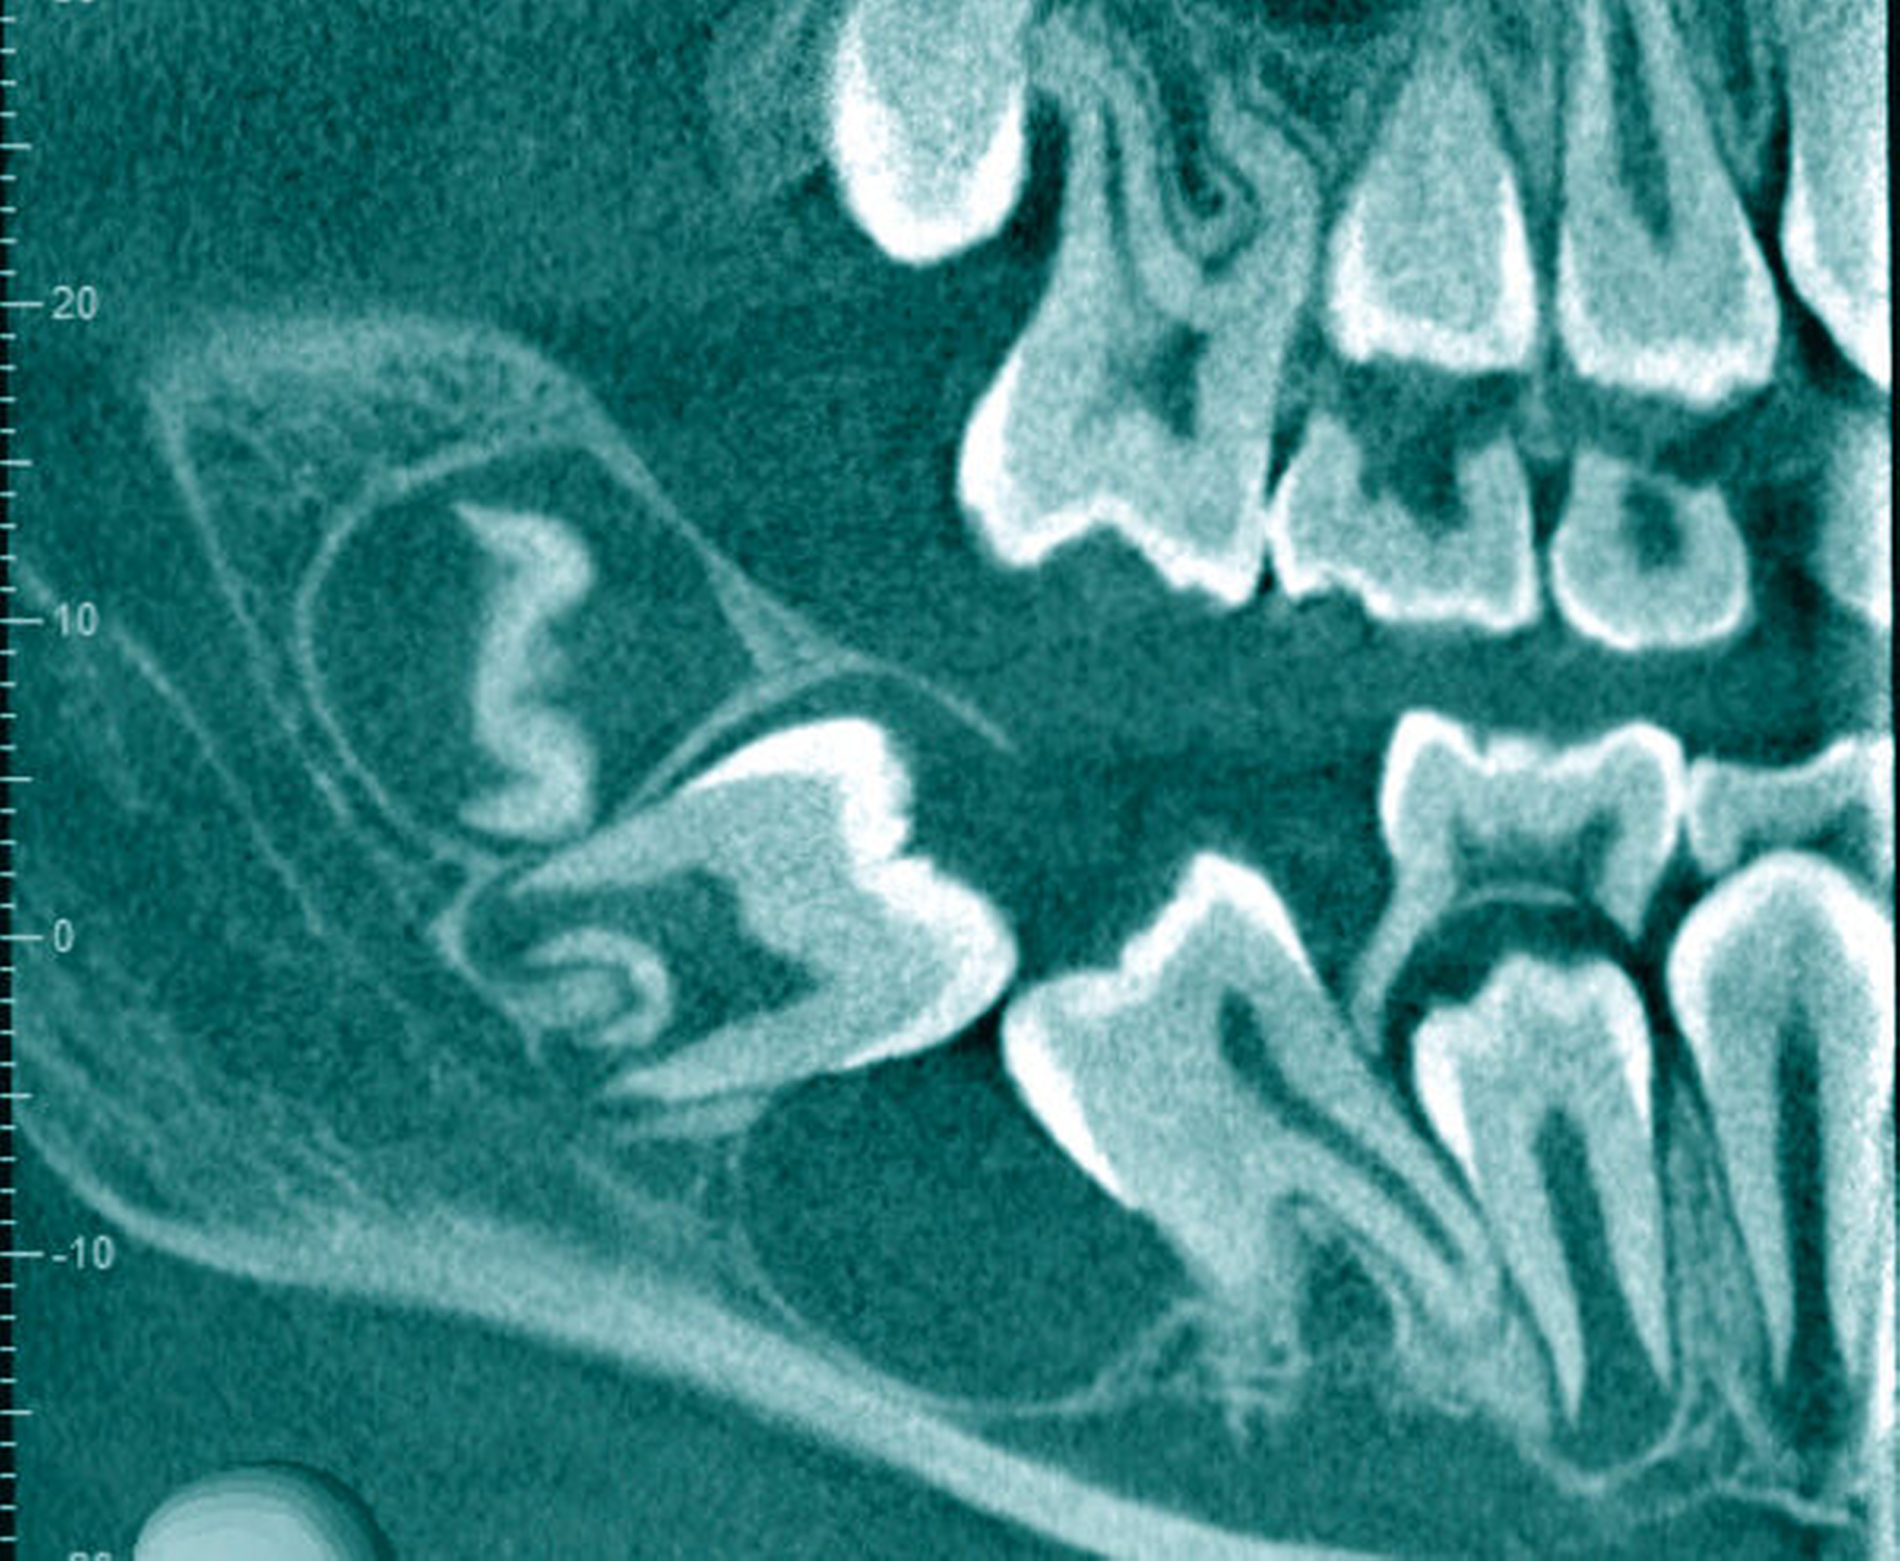

Klinisch präsentierte sich ein gesundes Kind ohne Vorerkrankungen oder auffällige Familienanamnese. Die Inspektion der Mundhöhle zeigte einen leicht verdickten Alveolarkamm im dorsalen 4. Quadranten. Bei Palpation gab der Patient keine Schmerzen an. Ein Fistelgang war nicht zu sondieren. Sensible oder motorische Ausfälle wurden nicht beobachtet. Zur erweiterten Diagnostik erfolgte eine Bildgebung mittels Digitaler Volumentomografie (Abbildungen 2 und 3). Hier bestätigte sich die zystische Raumforderung mit einer Ausdehnung von circa 2,5 cm x 2 cm. Die Kortikalis erschien intakt, wenn auch besonders im lingualen Bereich von geringer Stärke. Die Zähne 46 und 47 zeigten beide keine Zeichen von Resorptionen und der Canalis mandibularis konnte über seinen gesamten Verlauf nachverfolgt werden.